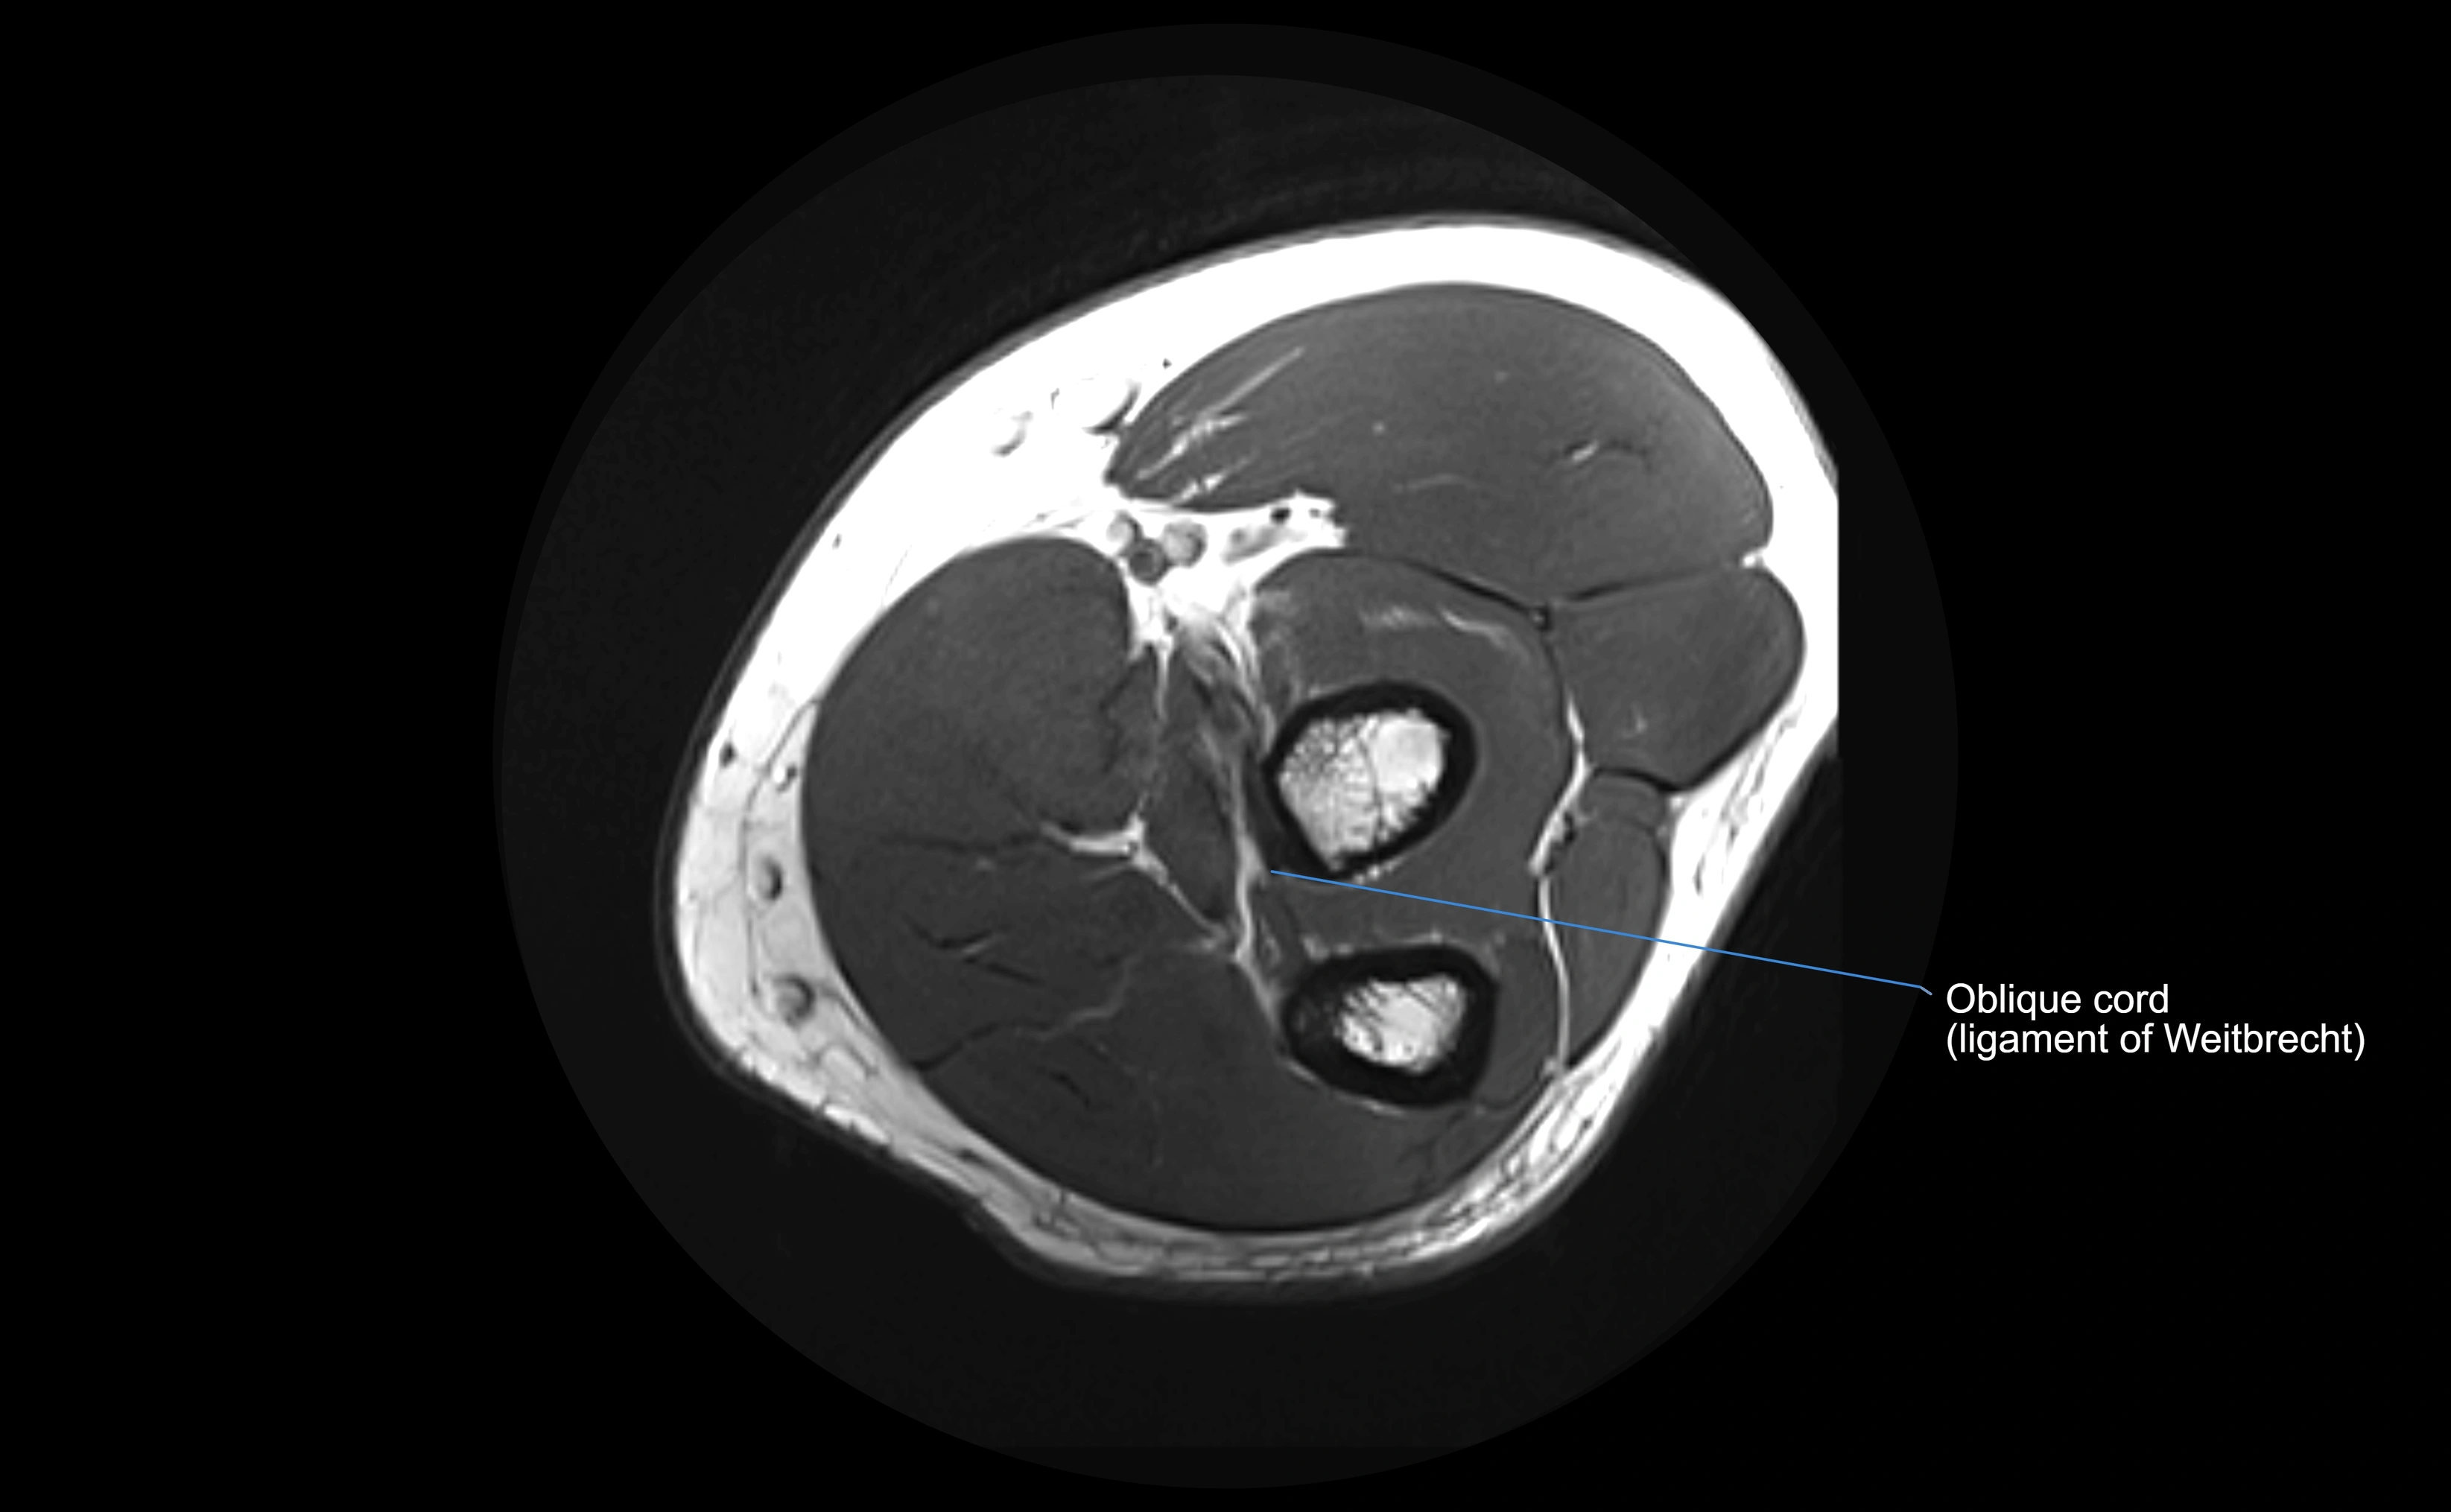

CT Appearance

Non-Contrast CT:

• Ligament not directly visualized due to soft-tissue density but may be inferred by the radial head’s containment in the notch.

• Bony margins of the radial notch and radial head appear smooth and congruent in normal anatomy.

• Avulsion injuries: subtle cortical irregularity or small bone fragments at ulnar attachment.

• Chronic cases: periarticular calcifications or ossification along ligament attachment.

CT Arthrogram Appearance

• Contrast fills the proximal radioulnar joint and outlines the radial head.

• Normal annular ligament: appears as a smooth, thin ring confining contrast to the joint space.

• Partial tear: contrast seeps beneath ligament or into adjacent soft tissues.

• Complete tear or dislocation: contrast extravasates around the radial neck or ulnar radial notch.

• Highly effective for evaluating joint congruency, ligament integrity, and subluxation when MRI is unavailable or contraindicated.